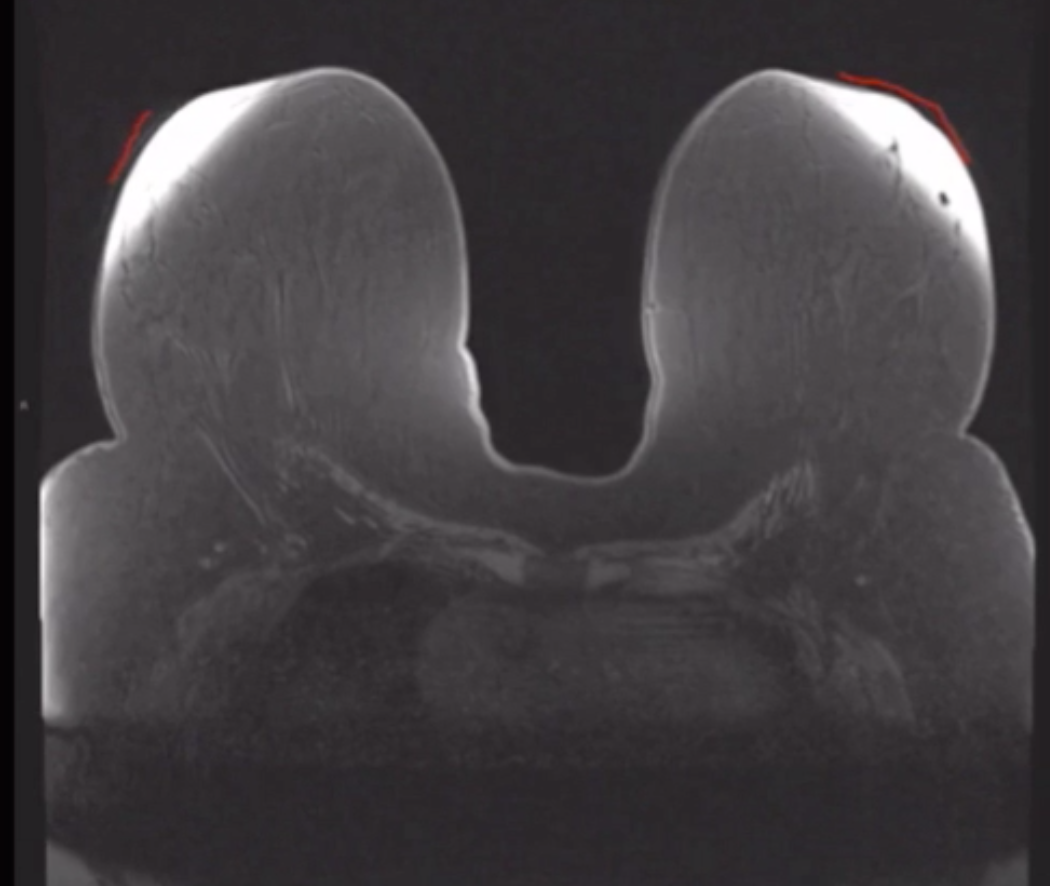

Fat saturation

• Poor fat saturation in image below

Incomplete fat saturation

Flaring

• Non uniform fat suppression when breast tissue to too close to the coil

• NOT related to fat suppression process itself

• Fix by putting a pad between the breast tissue and coild